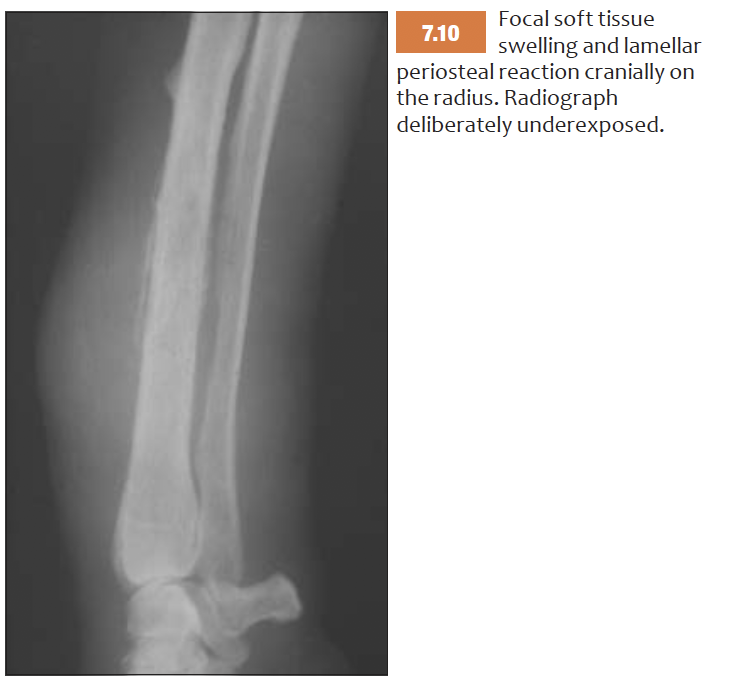

List features of lamellar (parallel) periosteal reaction

List features of Lamellated periosteal reaction